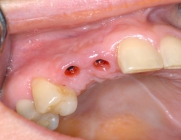

Since 1992, titanium screw implants have been inserted in edentulous sections of the upper and lower jaw in the clinic. Such dental implants serve as artificial tooth roots which, in combination with a tooth-crown-like superstructure (superstructure), enable the restoration of isolated tooth gaps with a crown, in the case of several missing teeth with a crown block, and finally in the case of an edentulous jaw with a fixed prosthesis.

One of the prerequisites for a successful and durable implant restoration is sufficient height and width of the remaining jaw bone. A special focus of the clinic is to create a favorable implant site for implantation by depositing autologous bone or bone substitute materials in the maxilla by introducing the bone into the maxillary sinus.